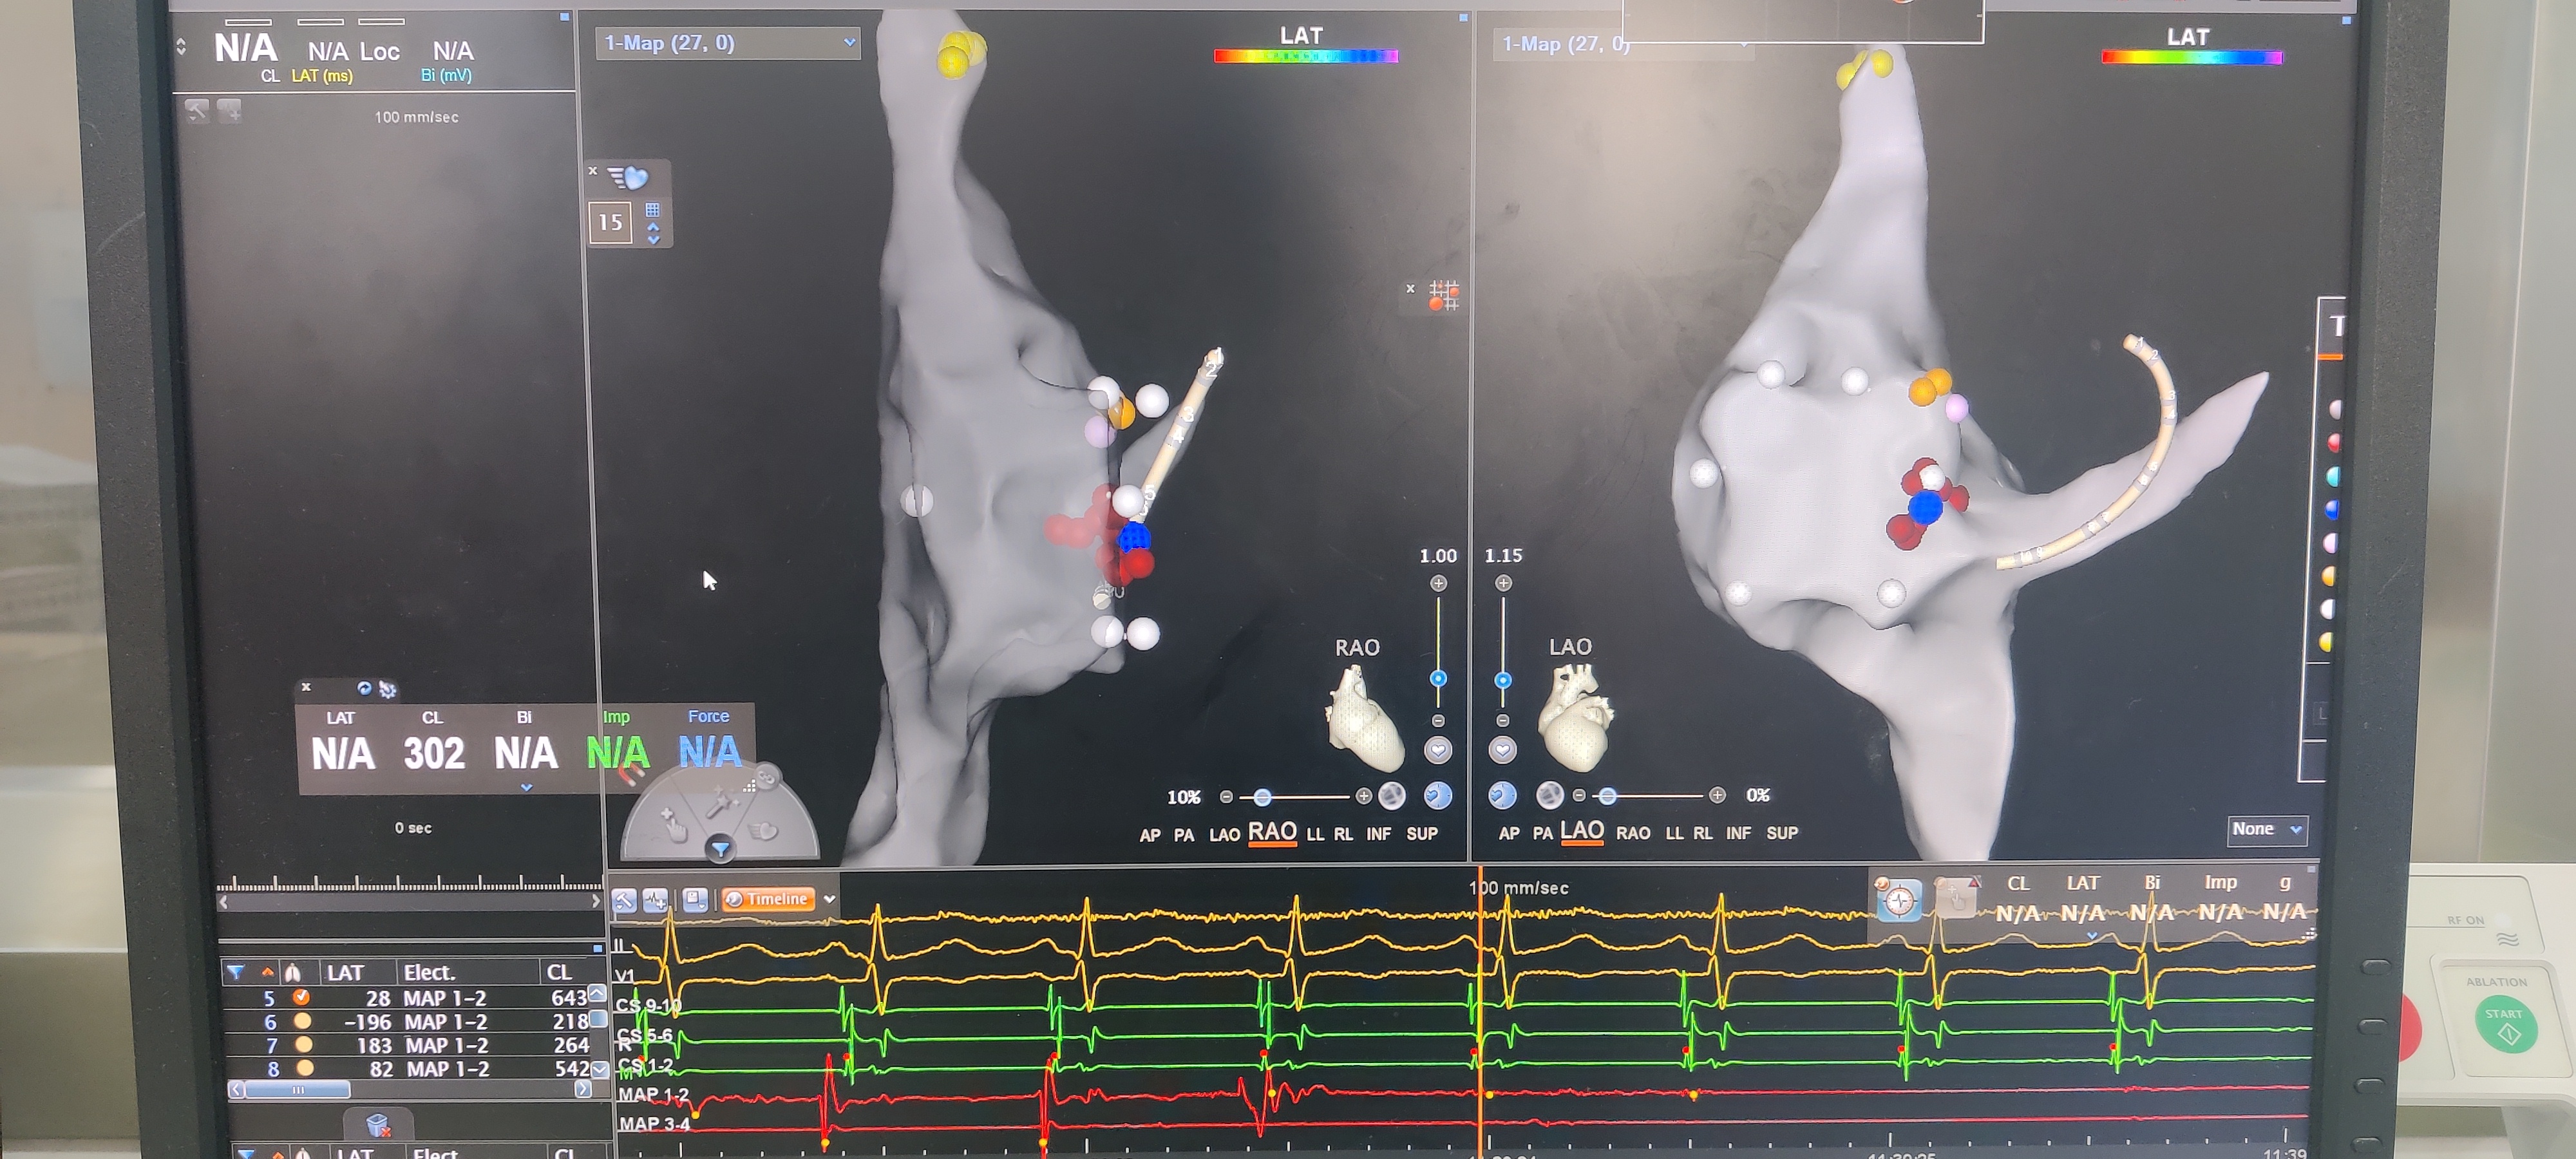

1月1日凌晨,孕26周的准妈妈罗女士(化名),自觉呼吸困难伴胸闷,她知道这是自己的老毛病心动过速发作,但此次和以往有加重,既往自己摸索有效的终止方式都不能缓解,当地医院给予了药物处理,虽能短暂终止,但很快又发作了。立即与家人赶往陆军军医大学新桥医院。但进入医院后,她的头晕、心慌、呼吸不畅的症状加剧。医生在为其心电监护期间,心率不断升高,最高达180次/分(正常人心率一般为60-100次/分),心内科电生理组谭虎团队为其确诊是妊娠合并阵发性室上速,情况十分危急,孕妇和胎儿随时可能有生命危险。 原来罗女士在13岁曾经因为阵发性室上速做过一次射频消融,术后没再发作心动过速,这次怀孕1个多月时候,再次出现心动过速,心率高达170-190次/分,开始还能自行终止,后面随着孕期进展,发作越来越勤,以至于近期需要到外院静脉推注药物才能终止。 “患者心动过速考虑是阵发性室上速发作,诱因可能是妊娠,随着孕期的增加,发作可能会越来越频繁。目前安全终止孕妇室上速的药物疗效比较短暂,不能长期有效控制心动过速发作,而心率长期处于高水平的180次/分左右,可能很快会诱发心力衰竭等症状,会严重影响孕妇和胎儿的安全。有些高敏孕妇可能数小时或者数十小时就会出现这类情况。只有再次射频消融术才能控制住。但同时也要注意围术期的操作对孕妇和胎儿的影响,尽量减少不必要的操作和检查,同时严密监测孕妇生命体征及胎儿发育情况。”心内科电生理组谭虎教授在会诊讨论后决定为患者在零射线下,实施射频消融术,终止罗女士的心动过速。 经过术前充分准备,在科室晋军主任的带领下,谭虎副主任率电生理团队通力合作,在产科老师的围术期支持下,在三维标测系统辅助下,全程零射线,找到病灶靶点之后,心动过速被成功终止,因为是二次射频消融术,术中也反复观察及验证,确保消融疗效。

“传统的射频消融,医生需要在射线下指导手术,射线可能对孕妇,尤其是对胎儿的发育造成影响。”谭虎教授表示,现在采用的是磁场、电场双重定位系统的三维标测系统辅导方法,全程零射线,在三维指导下来进行射频消融,通过这个三维标测系统辅导方法,能够精准找到引起心律失常机制的点,精准的把这个病灶去除,既没有副作用,又达到了一个非常完美的效果。” 术后检查显示,罗女士的心动过速现象完全消失,她和其他正常孕妇完全一样了,后面的孕期及生产都不会受影响。术后4天即可康复出院。 据新桥医院心内科主任晋军教授介绍,目前科室已经成功为多例孕妇成功实施了零射线下心脏介入手术,包括心脏起搏器植入,手术均已成功。该手术是一种“绿色”的电生理技术,可以避免辐射危害,该技术对伴有心律失常的孕妇及儿童实施此技术为最佳方案,然而零射线下的射频消融手术,不仅对设备的要求高,而且对手术医生的手术技术熟练程度、对导管的操作技术要求更高,同时需要医生、技师以及护理团队的紧密协作,最大限度地保护患者的健康。 |